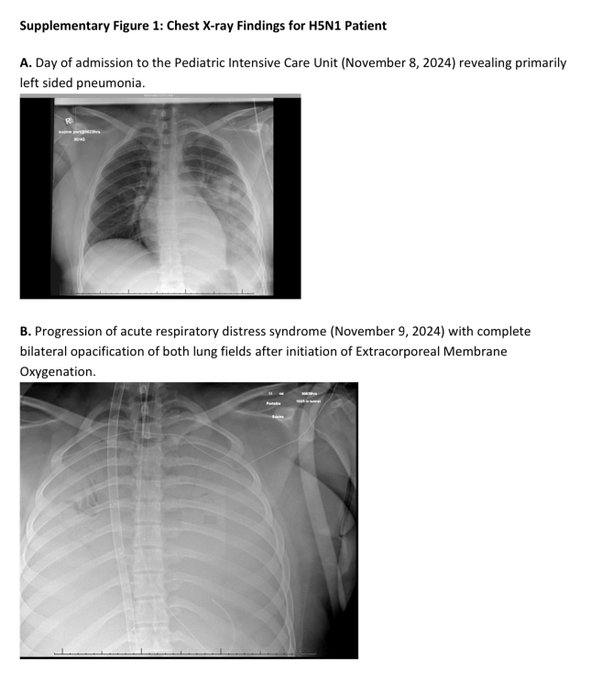

Linnugripist 13 aastase tüdruku näitel.

A 13-year-old in BC went from mild flu symptoms to full-blown respiratory failure.

Discharged after fever and conjunctivitis.

She came back days later in critical condition: pneumonia, kidney failure, leukopenia, and thrombocytopenia.

https://x.com/outbreakupdates/status/18 ... 2023946666

First description of a CRITICALLY ILL PAEDIATRIC PATIENT with H5N1 BirdFlu in North America.

The D1.1 virus circulating in BC birds almost KILLED this 13 yr old in less than 96 hours.

She presented in multi-organ failure 3 days after mild conjunctivitis.

Her lungs were WHITE-OUTS.👇👇

Only modern day organ support (ECMO/CVVHDF) saved her.

https://x.com/richardhirschs1/status/18 ... 6838185438